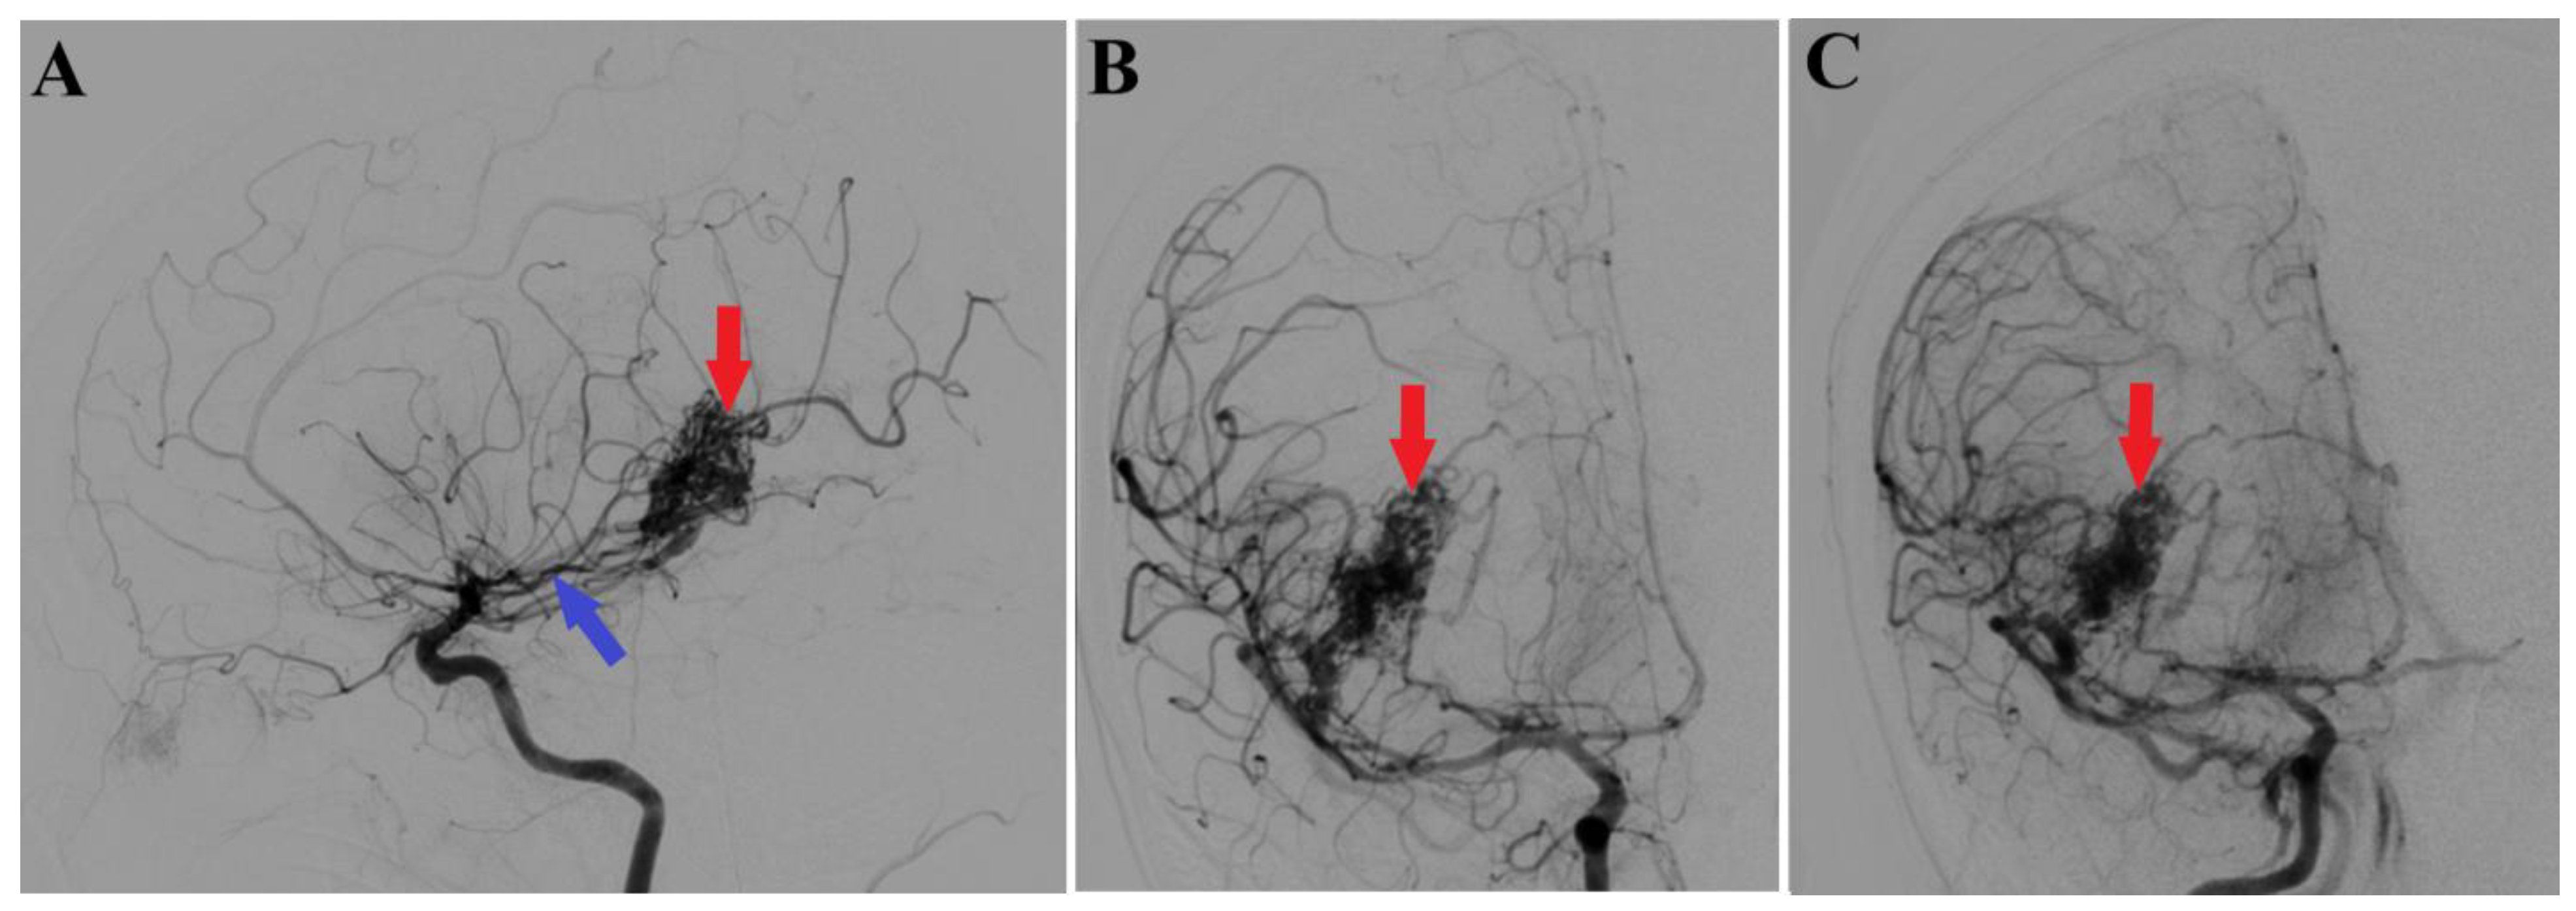

A 44-year-old patient was admitted to our clinic for sudden left hemiparesis MRC 1/5 occurring in the apparent health status 48 h prior to admission, followed by the deterioration of consciousness that become gradually worse, with the patient becoming comatose. She was admitted to our clinic with GCS = 7 points (eye response—2 points, verbal response—2 points, motor response—3 points), orotracheally intubated, and mechanically ventilated. Neurological examination on admission revealed a left hemiparesis, predominantly in the brachial region and comatose state. A brain non-contrast CT scan revealed a voluminous right fronto-temporal intraparenchymal hematoma with panventricular infiltration, significant mass effect on the right lateral ventricle, and 1.5 cm displacement of the midline. Otherwise, normal cerebroventricular CT appearance was seen (Figure 1). Angiography was performed through the selective injection of the internal carotid artery bilaterally, right external carotid artery, and left vertebral artery. Right temporal arteriovenous malformation with arterial afferents from the right anterior choroidal artery and right-sided middle cerebral artery was observed, Spetzler Martin grade III (Figure 2). A nidus of approximately 2/1 cm in size with several intranidal aneurysms was also observed (Figure 3). A single vein was draining into the right cavernous sinus, through an intermediate venous source.

Figure 2.

Preoperative 2D digital subtraction angiography. Profile (A) and frontal (B) 2D DSA highlights the right temporal arteriovenous malformation (red arrows), found as well in 2D DSA reconstruction (C). Moreover, profile 2D DSA (A) shows a slight dilatation of the anterior choroidal artery (blue arrow).